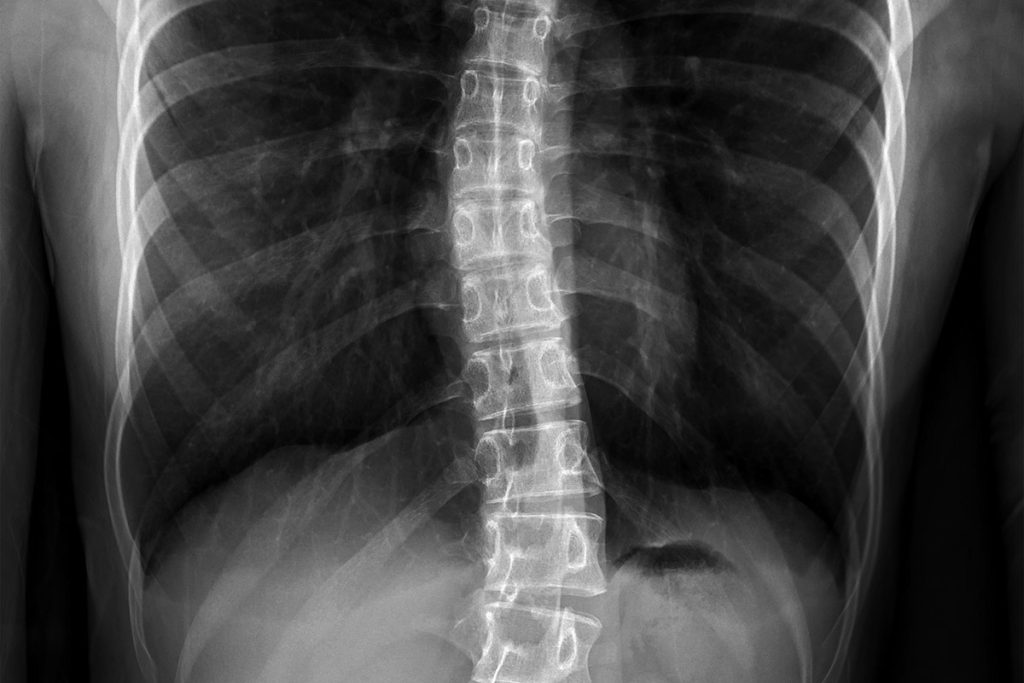

Основным методом диагностики сколиоза служит рентгенологическое обследование, которое позволяет оценить угол Кобба, отражающий выраженность искривления позвоночника. Первой стадии сколиотической болезни соответствует искривление до 9°, при последней угол Кобба превышает 75°.

Стандартная операция при сколиозе — спондилодез. Во время оперативного вмешательства с помощью специальных конструкций обездвиживаются определенные позвоночно-двигательные сегменты, что способствует сращению позвонков. В большинстве случаев такая операция эффективна, но у нее есть несколько существенных недостатков, включая ограничение потенциала роста позвоночника и свободы движений.

Недавно в России появилась альтернатива спондилодезу — вентральная динамическая коррекции позвоночника, которая может применяться как у растущих детей и подростков, так и у взрослых.

Преимущества операции — сохранение потенциала роста позвоночника, свободы движений, низкий риск кровопотери, короткий реабилитационный период. В отличие от стандартной операции, во время хирургического вмешательства мышцы спины не рассекают, поэтому пациенты очень быстро восстанавливаются. Реабилитационный период длится в среднем месяц. Через 1,5 месяца человек возвращается к неограниченной физактивности. В России первыми внедрили эту операцию в клиническую практику врачи медицинского центра им. Н.Н. Приорова.